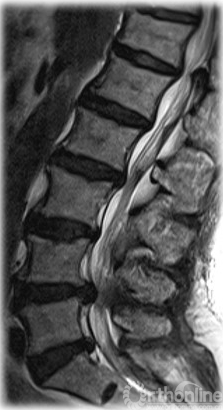

多节段腰椎退行性病变

术前诊断也是MP发生的危险因素,有学者将以下三类疾病的存在认为是MP的发生的危险因素:脊柱退行性病变;伴有脊柱后凸畸形的强直性脊柱炎;转移瘤、脊柱骨折。他们认为这可能与术前已存在的椎间盘退变或小关节增生造成的L2、3神经根损害有关。